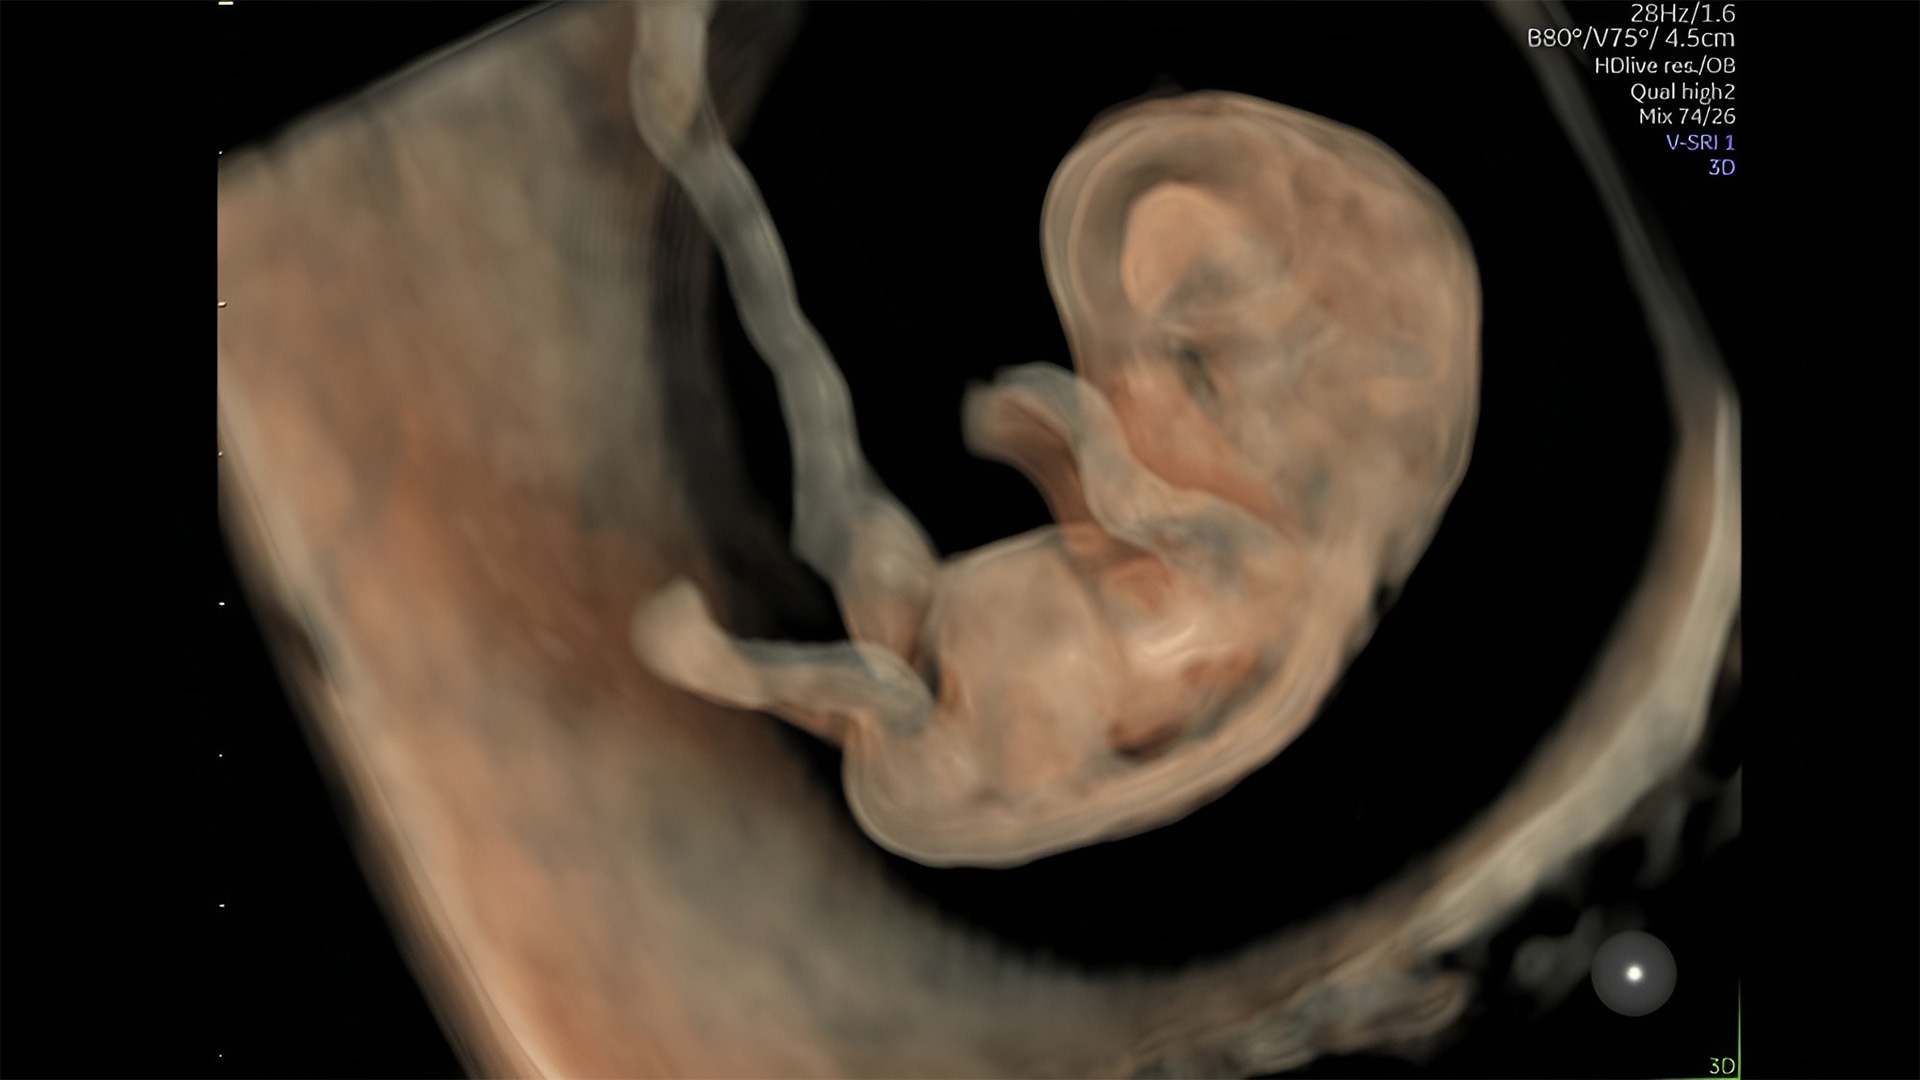

Discover complicated anomalies and pathologies with the Voluson Expert 22 to provide answers sooner for better decision making.

Complex cases come with enough uncertainty. That's why the Voluson Expert 22 is specifically designed for in-depth assessment of complicated anatomy — with pioneering first trimester, fetal cardiac, gynecological, and other pivotal technologies that focus on early detection and intervention.

First trimester exams

Perform detailed exams with high-resolution for early insights to fetal health